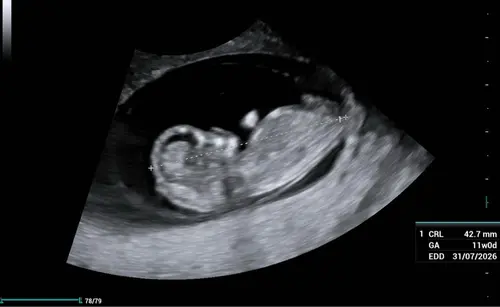

Zo intens spannend, van de eerste echo met 7+2 moeten wachten tot vandaag 11+2. Maar het was het wachten waard en we hebben een super goede 2e echo gehad! ❤️ datum stond al vast ivm icsi 01-08-2026, groei loopt wel 2 dagen voor 🤗🥰